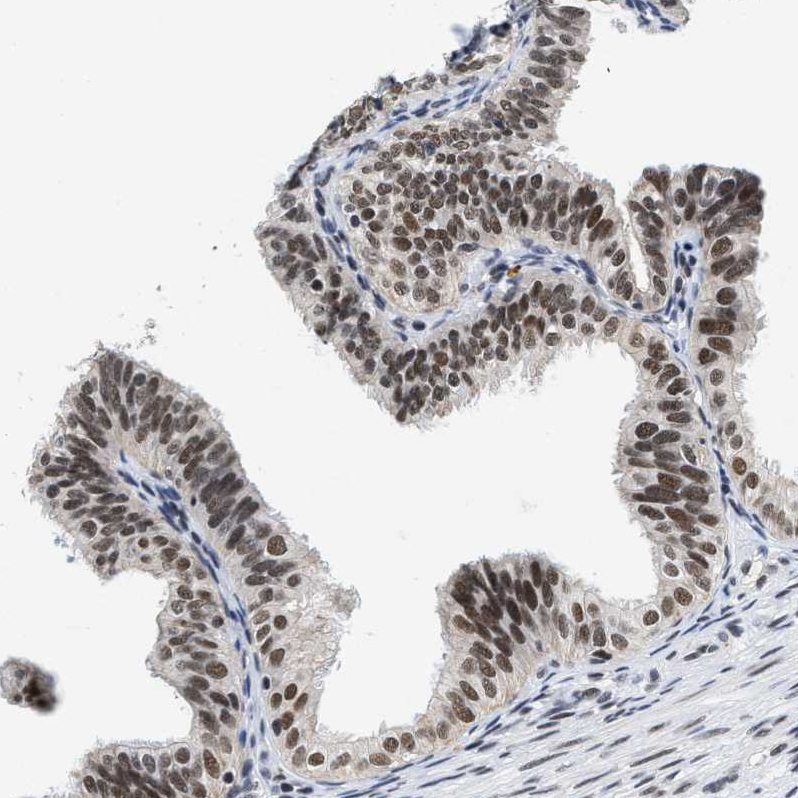

Immunohistochemistry analysis in human thyroid gland and skeletal muscle tissues using HPA020382 antibody. Corresponding INIP RNA-seq data are presented for the same tissues.